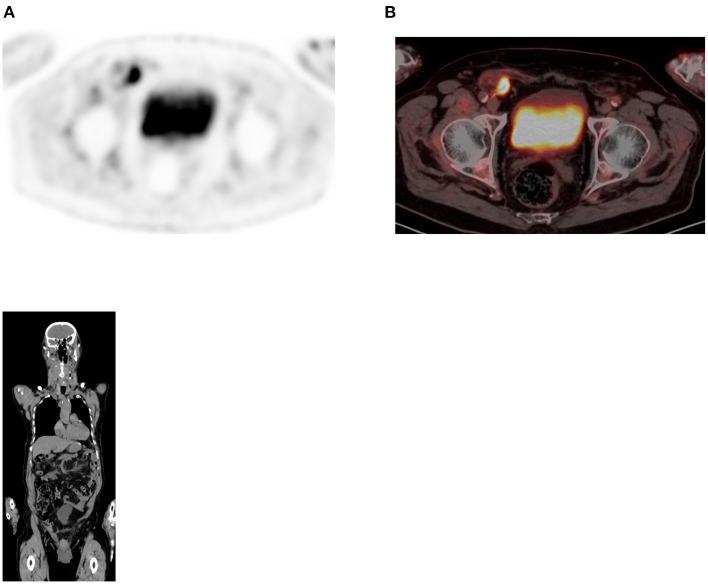

Since its introduction into clinical practice, multimodality imaging has revolutionized diagnostic imaging for both oncologic and non-oncologic pathologies. F-fluorodeoxyglucose (F-FDG) PET/CT imaging which takes advantage of increased anaerobic glycolysis that occurs in tumor cells (Warburg effect) has gained significant clinical relevance in the management of most, if not all oncologic conditions. Because FDG is taken by both normal and abnormal tissues, PET/CT imaging may demonstrate several normal variants and imaging pitfalls. These may ultimately impact disease detection and diagnostic accuracy. Imaging specialists (nuclear medicine physicians and radiologists) must demonstrate a thorough understanding of normal and physiologic variants in the distribution of F-FDG; including potential imaging pitfalls and technical artifacts to minimize misinterpretation of images. The normal physiologic course of F-FDG results in a variable degree of uptake in the stomach, liver, spleen, small and large bowel. Urinary excretion results in renal, ureteric, and urinary bladder uptake. Technical artifacts can occur due to motion, truncation as well as the effects of contrast agents and metallic hardware. Using pictorial illustrations, this paper aims to describe the variants of physiologic F-FDG uptake that may mimic pathology as well as potential benign conditions that may result in misinterpretation of PET/CT images in common oncologic conditions of the abdomen and pelvis.

自从多模态成像技术引入临床实践以来,它已经彻底改变了肿瘤和非肿瘤疾病的诊断成像。利用肿瘤细胞中发生的无氧糖酵解增加(瓦伯格效应)的F-氟脱氧葡萄糖(F-FDG)PET/CT成像,在大多数(即使不是全部)肿瘤疾病的管理中已具有重要的临床意义。由于正常组织和异常组织都会摄取FDG,PET/CT成像可能会显示出几种正常变异和成像陷阱。这些最终可能会影响疾病检测和诊断准确性。成像专家(核医学医师和放射科医生)必须充分了解F-FDG分布中的正常和生理变异;包括潜在的成像陷阱和技术伪影,以尽量减少对图像的错误解读。F-FDG的正常生理过程会导致胃、肝脏、脾脏、小肠和大肠出现不同程度的摄取。尿液排泄会导致肾脏、输尿管和膀胱摄取。由于运动、截断以及造影剂和金属硬件的影响,可能会出现技术伪影。本文旨在通过图片说明,描述可能模仿病变的生理性F-FDG摄取变异,以及在腹部和骨盆常见肿瘤疾病中可能导致PET/CT图像误判的潜在良性情况。